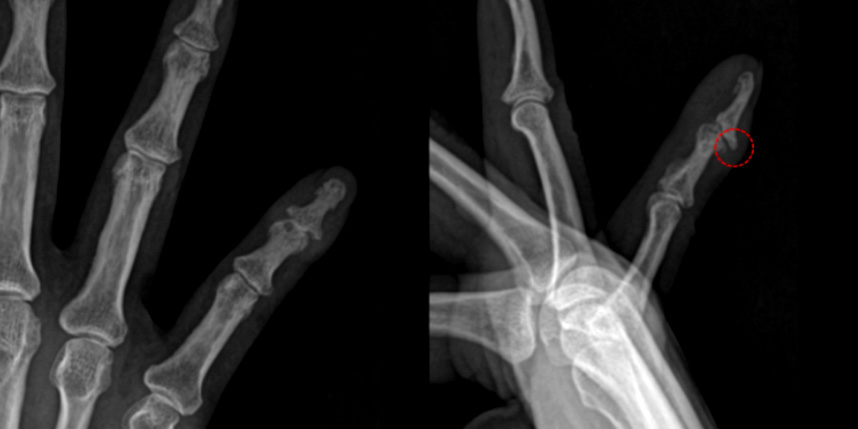

단순히 끝마디 관절염만 있을 때 골극 절제술을 잘 시행하지는 않지만 점액낭종이 생겨 손톱 변형이 있고 통증이 있을 때 점액낭종 절제술과 함께 골극 절제술을 같이 시행해볼 수 있습니다.

점액 낭종은 손가락에서 생기는 결절종이기 때문에 결절종과 마찬가지로 다음 사진처럼

관절과 연결된 뿌리를 잘 찾아가서 제거해주는 것이 재발을 줄이는 방법입니다.

피부가 얇아져 있어서 피부를 일부 같이 포함하여 절제하는데, 피부 결손이 큰 경우 피부 이식이 필요한 경우도 있습니다.

* 환자에게 받은 소중한 자료입니다.